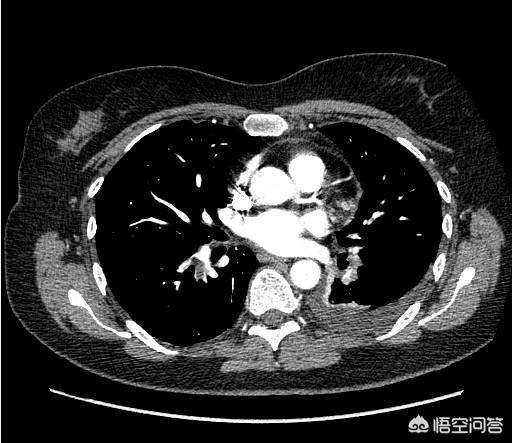

1.腹部全体のプレーンスキャン+強調CT

腹部CTにもplainとenhancedがあることを知らない人が多い。何が違うのでしょうか?腹部全体のCTスキャンは安く、全体像を見るのに数百円です。さらに詳しく見るには、造影・強調CTを受ける必要があります。造影・強調CTとは、検査中に血管に薬を注入し、動脈や静脈の血管を強調CT画像で可視化するものです。すべての腹部臓器には血液を供給する血管があるため、プレーンCTよりも各臓器が鮮明に映し出されます。

例えば、私は外来で患者を診察している。その患者はまず超音波検査を受け、肝臓に特徴的でない腫瘤を発見する。このとき、プレーンCTだけでは、腫瘤の性質を判断することができないかもしれません。スキャン+強調CTでは、造影剤を使わないスキャンCTで腫瘤がどのように見えるかを観察することができます。造影ありの場合は、肝臓の血管を造影剤で満たしたときに腫瘤がどのように見えるかを観察します。肝がんの画像的特徴に基づいて、その腫瘤が肝がんであるかどうかを判断します。

プレーンCTとエンハンストCTを組み合わせることで、腹部の腫瘍を動的に見ることができる。腹部の臓器は固形臓器と中空臓器に分けられ、CTは胃の固形臓器(肝臓、膵臓、脾臓など)によく効き、中空臓器(消化管、尿管など)には効きにくい。そのため、胃カメラと大腸カメラという2つの検査を追加する必要がある。